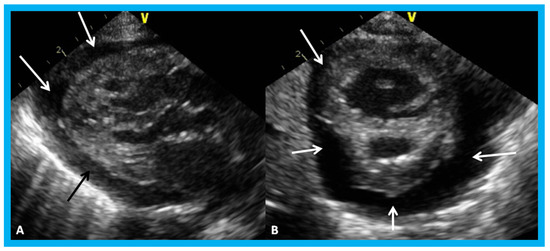

Figure 24. Apical four-chamber views of the left ventricle (LV) in end-diastole (LVED) in (A) and end-systole (LVES) in (B) demonstrating calculation of area shortening of the LV using Simpson’s rule: AS = (LVAd − LVAs)/LVAd (where AS is area shortening, LVAd is LV area in diastole, and LVAs is LV area in systole). The LV area shortening is 52% (see insert in (B)); normal values are 40 to 60%.